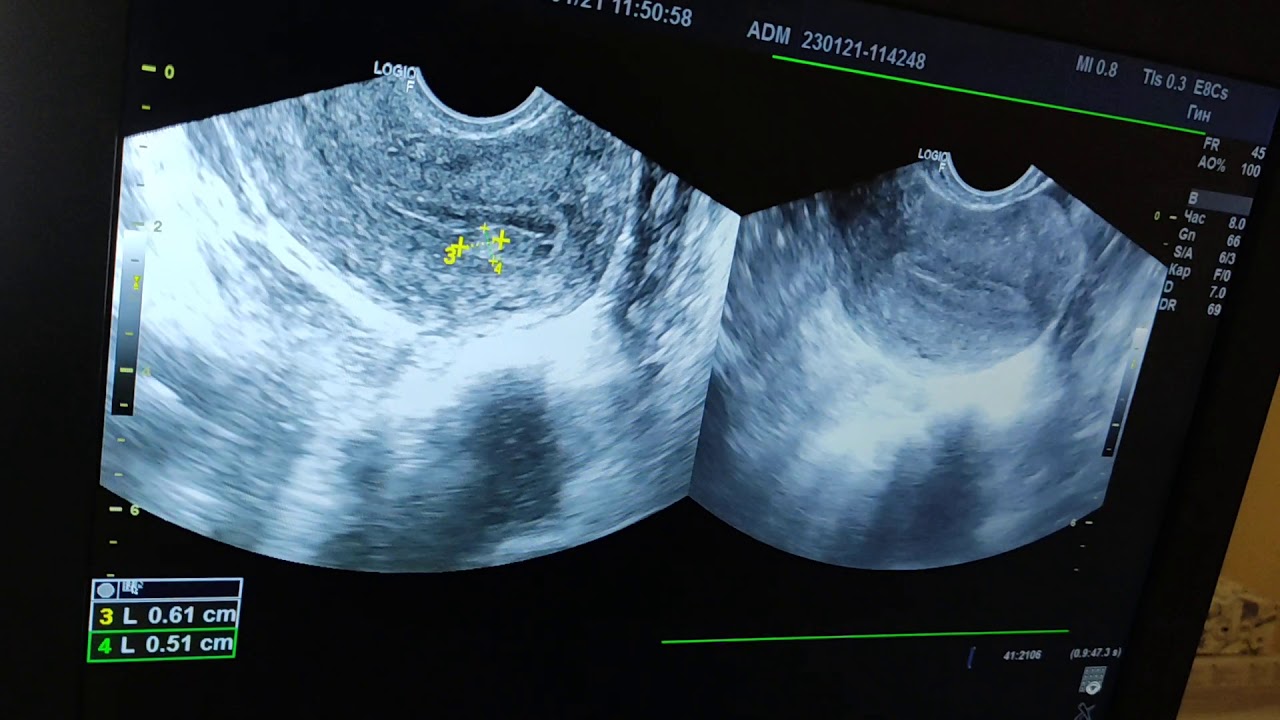

Признаки полипа эндометрия на УЗИ

На основании чего доктор ставит диагноз? Специалист знает, как он выглядит на снимке. Ниже приведено фото, на котором изображен полип.

Конечно, заключение должен делать не сонолог, а опытный гинеколог. Сонолог лишь указывает подозрительные моменты на снимках и ставит предварительный диагноз. Врач оценит эхогенность органов. На что он обратит внимание?